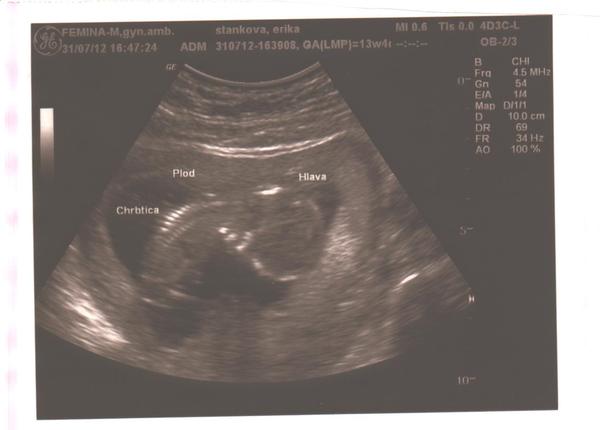

Tak ako Ti píše @sabaka to že Ti býva tak zle znamená,že drobček je zdravý 😉 ,ja viem ako Ti je,neboj,nuž čo sa týka dobre najedenia sa tak ja som sa jedine zeleninou a ovocím mohla najesť a slepačov polievkov a od vtedy veľa neviem jesť ja som od pôrodu schudla už 11kg a malý má presne tých 11kg😀čo už neboj akonáhle budeš cítiť pohyb drobca bude Ti lepšie prejde vracanie a budeš vedieť lepšie jesť,alenech ťa neprekvapí,ak si budeš viac žiadať zdravé jedlá ako mastné a korenené či sladkosti po toľkom vracaní Ti budú ťažké a nebudeš ich moc chieť.Prajem krásne tehulkovanie 😉 A to vám tým sonom tam napísal lekár hlava,plod a chrbtica?Krásne bábo,veľa zdravíčka vám obom prajem🙂